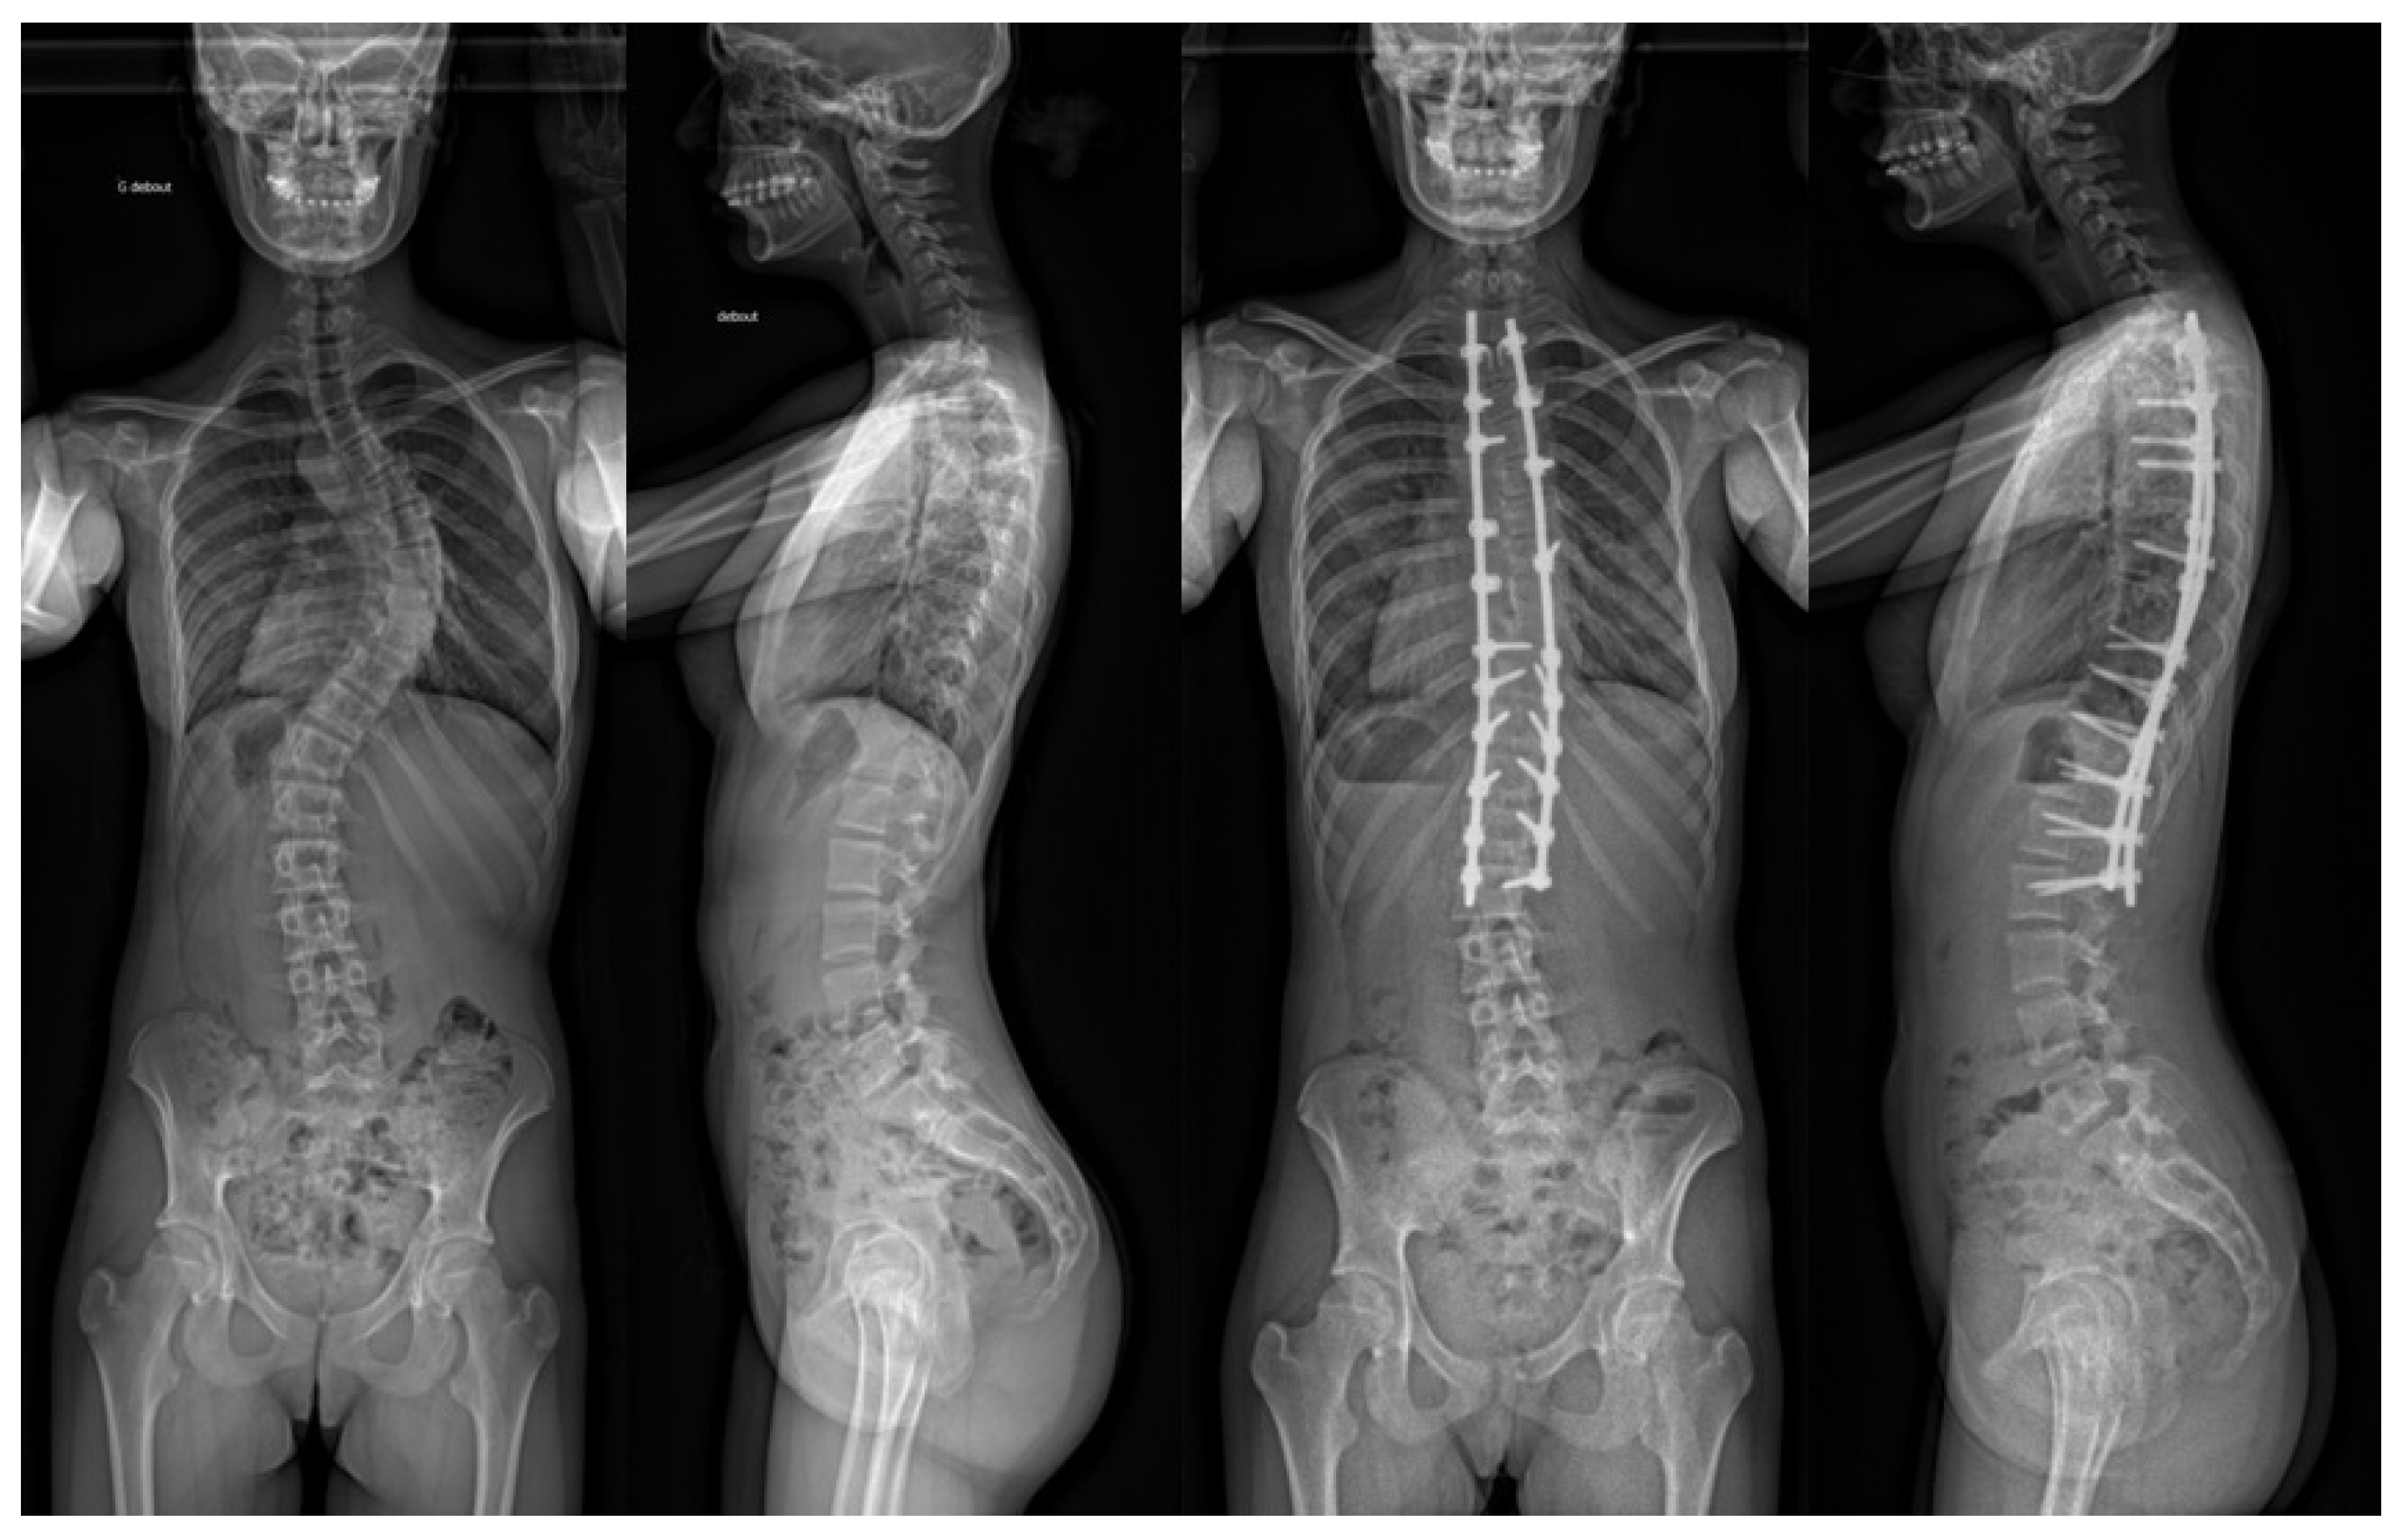

Safety and Efficacy of Stand-Alone Bioactive Glass Injectable Putty or Granules in Posterior Vertebral Fusion for Adolescent Idiopathic and Non-Idiopathic Scoliosis

2.2. Surgical Technique

3.4. Radiographic Analysis